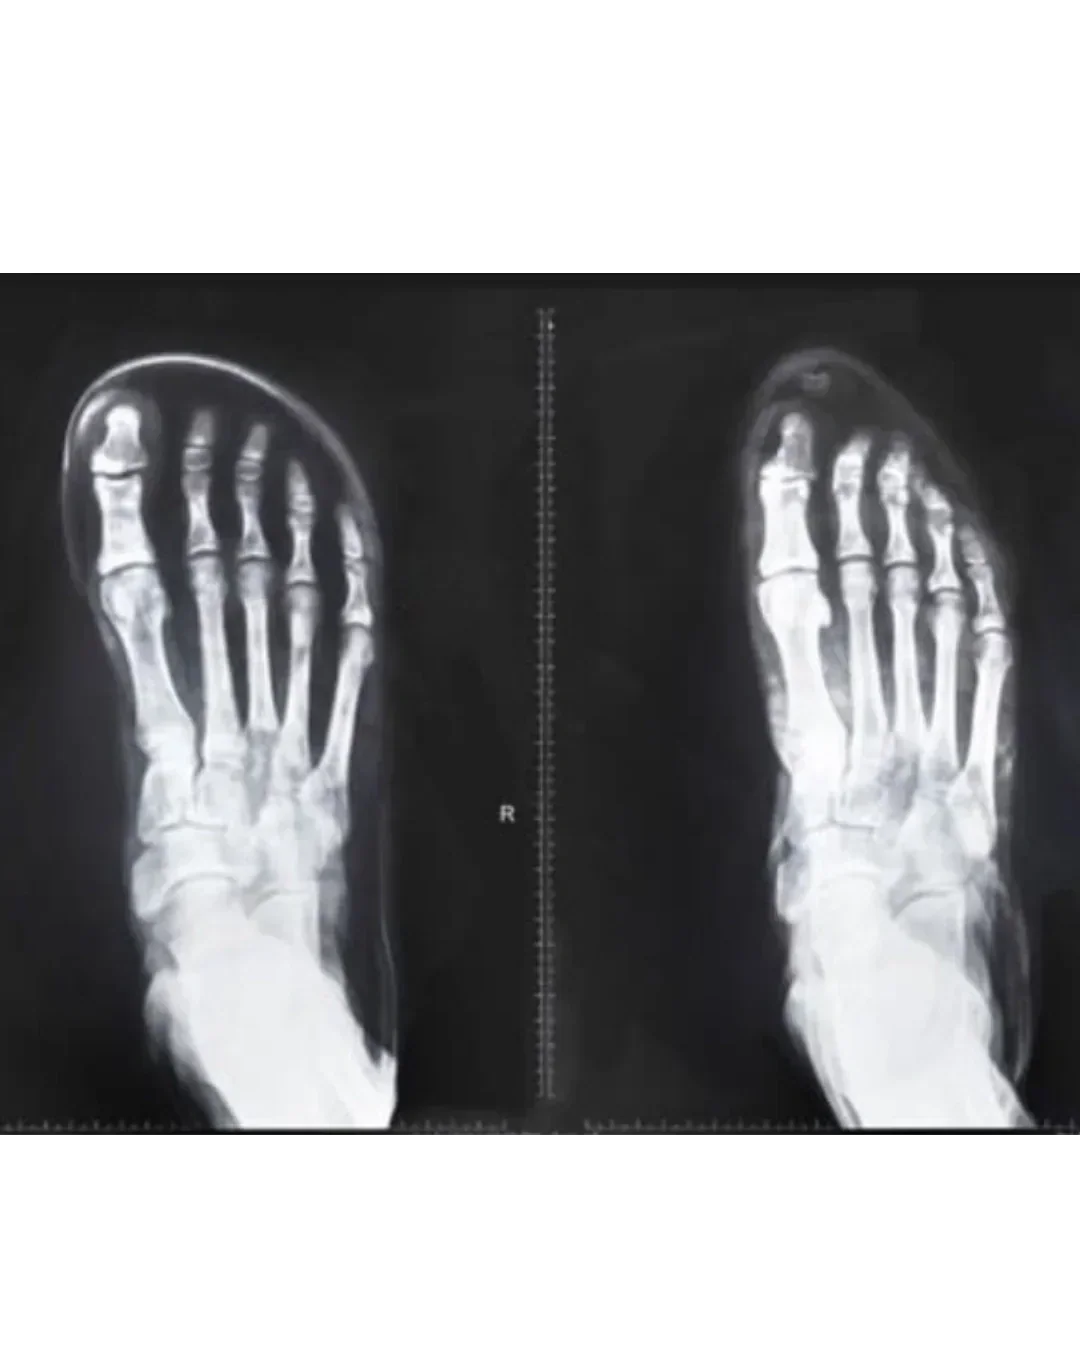

1. Narrow Toe Boxes

Most shoes taper toward the front, squeezing your toes together. This can:

Push your big toe inward (leading to bunions and deformities)

Reduce toe splay, which is essential for balance

Limit power in your push-off when walking or running

Research links restrictive footwear to higher forefoot pressure and increased risk of bunions. Wider footwear designs can reduce discomfort and improve stability.